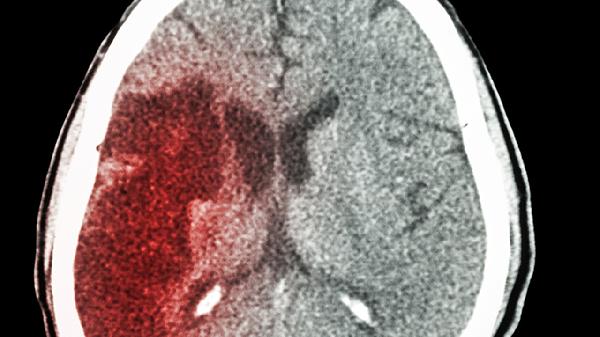

心脑供血不足可能与动脉粥样硬化、高血压、颈椎病、心脏泵血能力下降以及血液黏稠度增加等因素有关。这种状况常表现为头晕、头痛、视力模糊、肢体发麻、记忆力减退等,可以通过调整生活习惯、控制原有疾病和药物干预来改善。

动脉粥样硬化是导致心脑供血不足的常见因素,通常与长期高脂饮食、吸烟等不良习惯相关,容易在血管内膜上形成脂肪沉积物,逐渐发展成斑块。这些斑块会堵塞或狭窄血管,进而影响脑部或心脏的供血。患者可能会出现胸闷、眼前发黑等症状。治疗上需根据医生建议使用阿托伐他汀钙片、氯吡格雷等药物,并注意饮食清淡低脂。2、高血压

如果高血压长期得不到有效控制,容易引发脑血管痉挛或动脉硬化,从而影响大脑供血。血压波动较大时,可能出现突发性眩晕、恶心呕吐等表现。治疗方面,应按时服用苯磺酸氨氯地平、厄贝沙坦等降压药,同时每日监测血压并减少食盐摄入。3、颈椎病